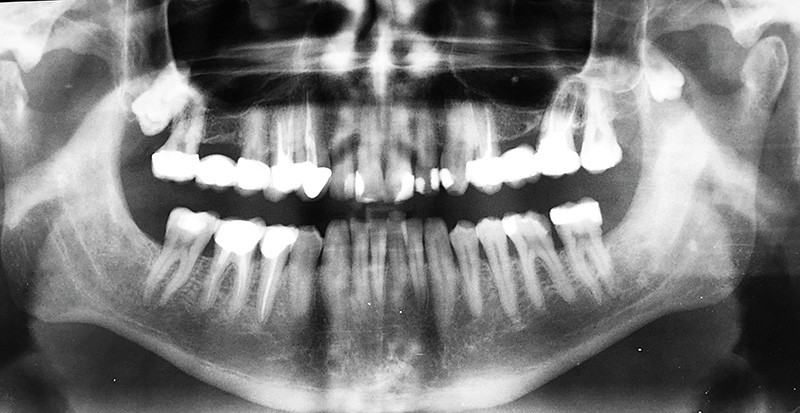

Réponses 1 : b et c ; 2 : b et d ; 3 : a

Commentaires

Il est impératif d’extraire 38 incluse ectopique (coroné) et d’énucléer la lésion kystique en rapport. Il est donc envisagé de réaliser une résection du coroné, ce qui permettra d’éviter une migration de la dent de sagesse dans la fosse infra-temporale (fig. 3).

L’intervention est réalisée sous anesthésie générale avec intubation orotrachéale ; mise en place d’une cale molaire controlatérale.

La voie d’abord est vestibulaire inférieure postérieure gauche remontant au niveau de la muqueuse jugale ; rugination de l’angle mandibulaire, corticale externe, du bord antérieur du ramus et de la corticale interne en sus-spigien.

Progressivement, une désinsertion musculaire est réalisée au niveau du coroné après repérage de l’échancrure du coroné.

L’ostéotomie est réalisée partant du bord antérieur du ramus jusqu’au niveau de l’échancrure. Un fil d’acier a été positionné au-dessus de l’ostéotomie de manière à…